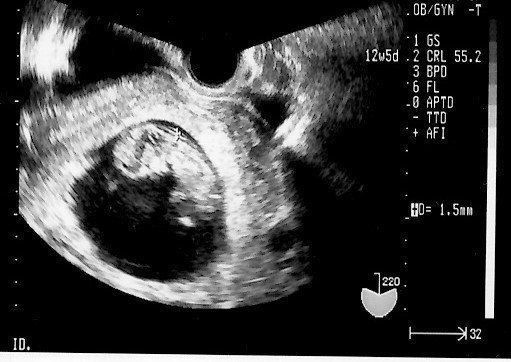

妊娠5週目のエコー写真 ようやく妊娠成立!

不妊治療専門クリニックで5回目の体外受精を行い、その後医師から妊娠していることを告げられました。妊娠5週目の画像です。当時は、妊娠したうれしさより、正直なところ「これでもうあの治療のつらさから解放されるかもしれない」という気持ちの方が強かったです。まだ流産の可能性が高いということで、夫も私も心から喜ぶことはできませんでした。